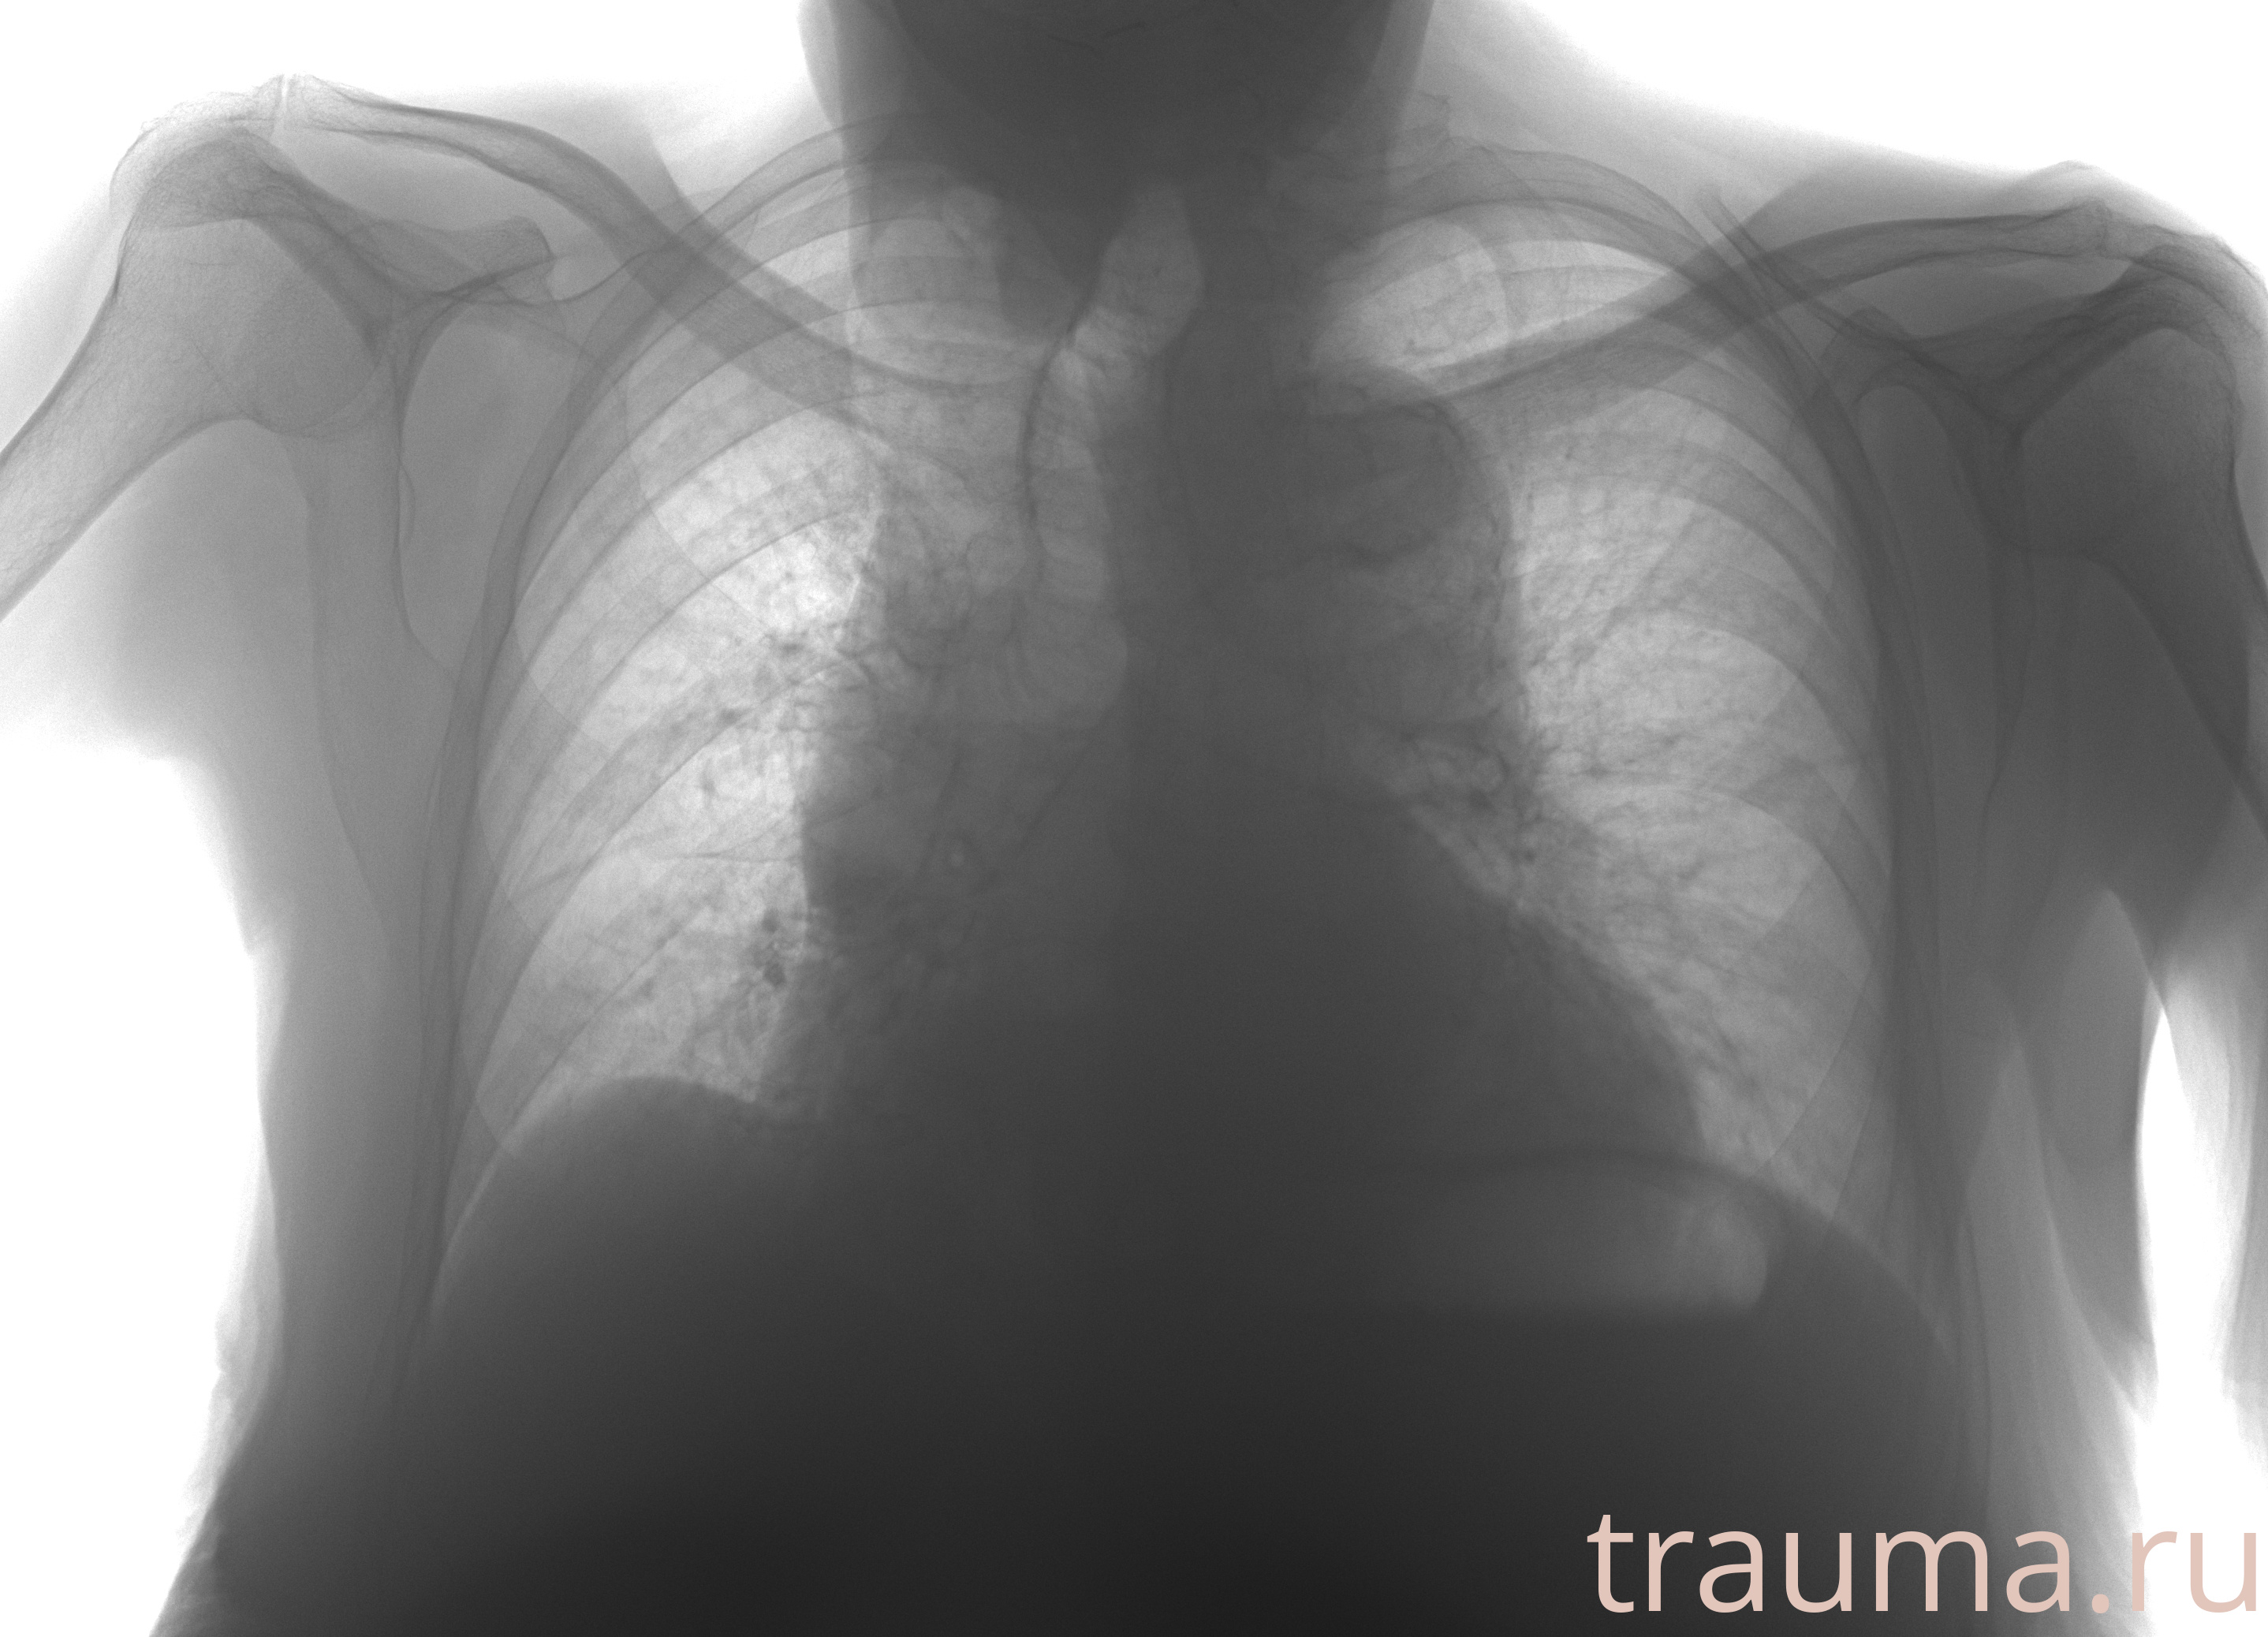

Рентген на дому: по вашему адресу приезжает врач-рентгенолог, травматолог-ортопед с мобильным рентгеновским аппаратом, проводит диагностику травмы или заболевания, делает необходимые рентгенограммы, дает рекомендации по дальнейшему лечению. Получить качественные снимки в домашних условиях возможно благодаря уникальной методике, разработанной МосРентген Центром для института  Склифосовского